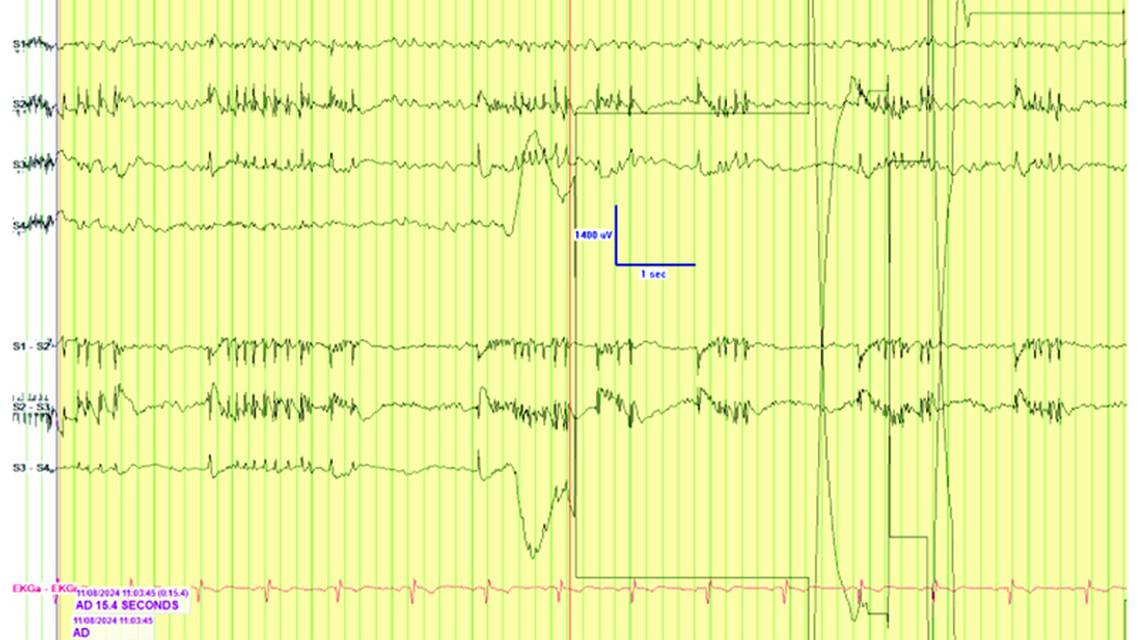

Figure 2. Spontaneous focal periodic epileptiform discharges (A), an afterdischarge present in a subdural strip array following direct electrical stimulation of the brain (B), and a focal afterdischarge present following direct electrical stimulation of the brain within the aperture of the hollow circular grid (C). Note the 2 channels obscured by artifact on the strip electrode in (B) (channel 1 used as reference, with 1–6 separated by 1-cm interelectrode distances) and the restricted field involving 3 electrodes in (A) recorded using the hollow circular grid (channel 22 used as a reference, with 0.5-cm interelectrode distances). Parameters of recording: Display speed, 30 mm/s; filter settings, 1–100 Hz; 60-Hz notch ON; sensitivity 50 μV/mm.